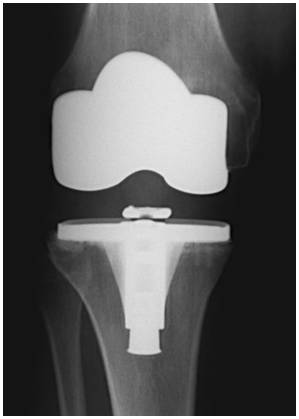

Introducción: El objetivo de este trabajo fue analizar los resultados funcionales y el rango de movimiento entre tres grupos de pacientes con artroplastia total de rodilla: dos utilizando prótesis de alta flexión y el otro con un diseño convencional. Materiales y Métodos: 64 pacientes fueron operados con prótesis total de rodilla Zimmer NexGen®, y 34 pacientes operados con Optetrack ® de alta flexión. Luego de la exclusión de pacientes; 22 pacientes (grupo A) fueron tratados con diseño de alta flexión de Zimmer, 21 pacientes (grupo B) tratados con prótesis Zimmer convencional, y 25 pacientes (Grupo C) con artroplastia Optetrack® PS. La evaluación funcional se realizó con el Knee Society Score, el Western Ontario and McMaster Universities osteoathritis index y la escala analógica visual. Resultados: En el posoperatorio, el promedio de flexión máxima del grupo A subió de 99° a 113º, con un aumento promedio de 14º, en el grupo B de 106° a 118º con una ganancia promedio de 12º y en el grupo C de 110° a 111° siendo la ganancia de 1°. Los resultados funcionales evaluados con KSS y el WOMAC presentaron mejorías en los tres grupos. Conclusión: Las evaluaciones clínicas funcionales son favorables en los tres diseños evaluados. Este estudio muestra que no hay diferencias significativas en la flexión final lograda, y resultados funcionales entre los dos primeros diseños entre sí, si siendo estos significativamente superiores al diseño del tercer grupo luego de un año de seguimiento. Palabras Claves: Prótesis total de rodilla, prótesis de alta flexión, prótesis convencionales, rango de movilidadDescargas